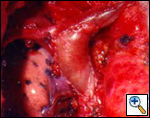

Tangential resection and venous plasty: in cases in which less than 30% of the SVC circumference is involved, a partial resection of the vessel can be performed. For minimal invasion, a tangential resection of the defect closed with a running suture or a vascular stapler is usually easy and leaves a patent vessel (Figure 6). Larger defects, especially if they are longitudinally extensive, require reconstruction; this can be obtained by the interposition of a patch of autologous or bovine pericardium (Figure 7). Autologous pericardium may be fixed in diluted glutaraldehyde (two drops of 20% glutaraldehyde in 50 cc of saline) for one minute to let it stiffen and facilitate manipulation during suturing.

SVC replacement: replacement of the whole body of the SVC is the most frequent type of reconstruction (Figure 8). In patients with lung cancer, it is usually associated with right upper lobectomy or pneumonectomy; however, SVC reconstruction may be required during carinal pneumonectomy, sleeve lobectomy (Figure 9), and reconstructive procedures of the pulmonary artery[5]; the latter two should always be attempted if they help to avoid pneumonectomy. SVC replacement requires a tumor–free confluence of both brachiocephalic veins. The reconstruction is usually performed using a straight non-ringed PTFE graft (18 – 20 mm). An autologous or bovine pericardial tube could also be used (Figure 10). After proximal and distal clamping, the SVC is excised. The proximal anastomosis is performed first, using a 5-0 polypropylene suture, starting from the posterior aspect of the prosthesis or the tube of pericardium. The distal anastomosis is subsequently performed with the same technique. Before tying the distal suture line, the proximal clamp is gently released and deaeration is performed; afterwards, the distal clamp is released and knots are tied. After complete filling of the graft by blood, there should be no tension of the suture lines or torsion or kinking.